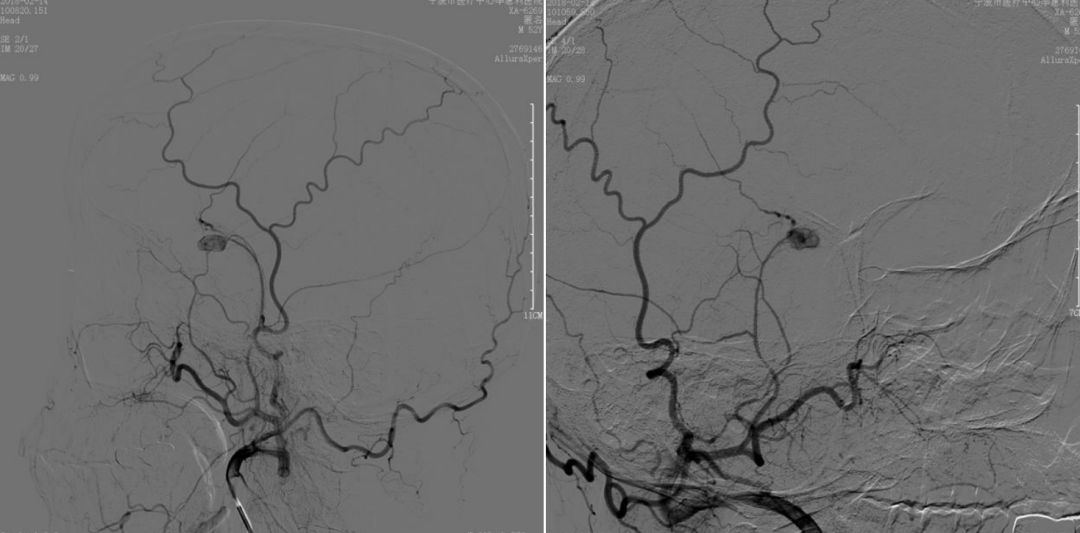

图7. 2018-2-14 DSA提示右侧脑膜中动脉假性动脉瘤。